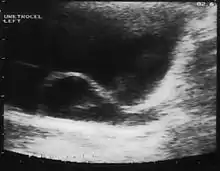

CT scan showing a ureterocele associated with a duplicated collection system of the left kidney.